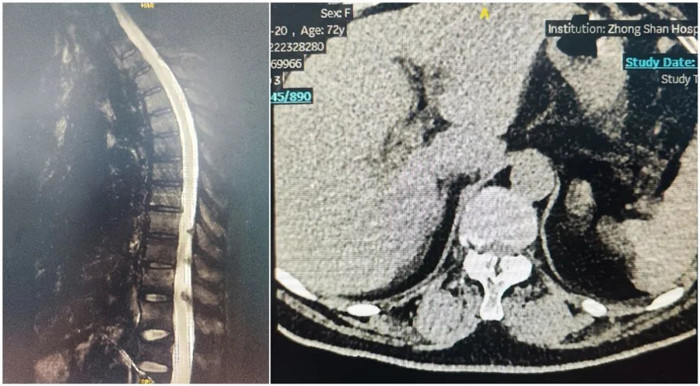

患者兩年前出現左側胸背部皮膚感覺麻木,有束帶感,左上臂皮膚感覺麻木,否認肌力減退,胸平掃椎CT示:胸椎序列正常,生理彎曲存在,椎體邊緣骨質增生,椎間盤略退變,T7-T9黃韌帶增生并伴骨化,壓迫內膜囊,椎管狹窄。影像診斷:黃韌帶骨化。

術前影像